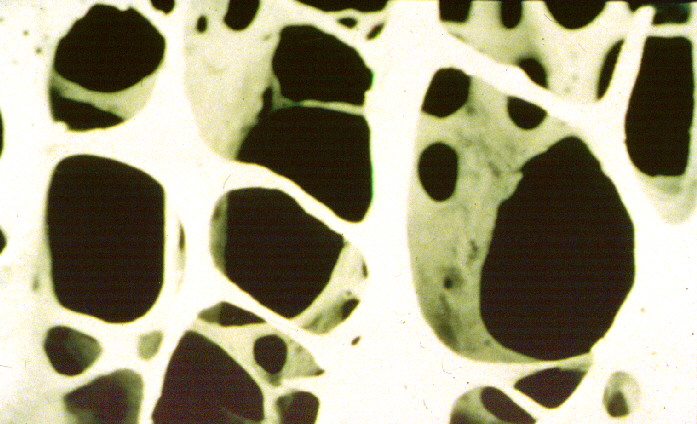

En gradvis reduksjon i beinmassen er en del av aldringsprosessen, se bilder nedenfor.

Osteoporose innebærer at beinets styrke er svekket; beinvevet blir mer porøst. Svekkelsen i beinstrukturen er en risikotilstand og gir ingen symptomer før man får et brudd. Risiko for å få et brudd i skjelettet øker gradvis ved lavere beintetthet. Når beintettheten har blitt så lav at man har osteoporose, vil risikoen for brudd være klart forhøyet.

Bildene viser normalt beinvev (øverst) og beinvev ved beinskjørhet (nederst). Vi ser at strukturene er tynnere og hulrommene større ved beinskjørhet.